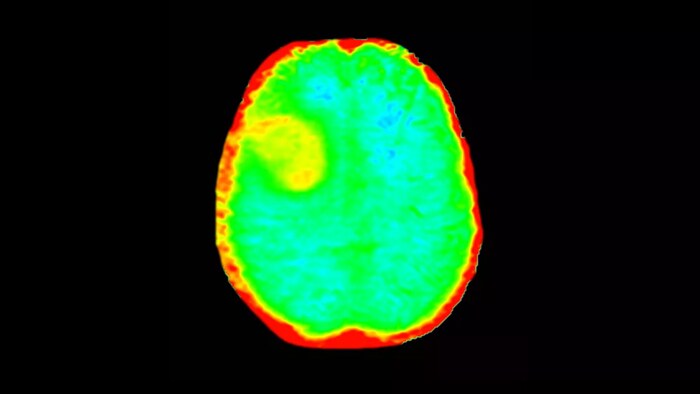

3D APT